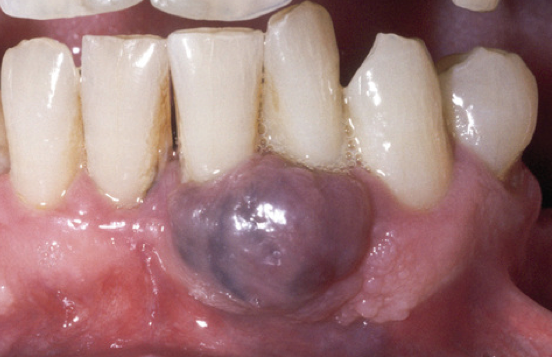

What is the likely Dx?

Peripheral giant cell granuloma NOTE it is more bluish.